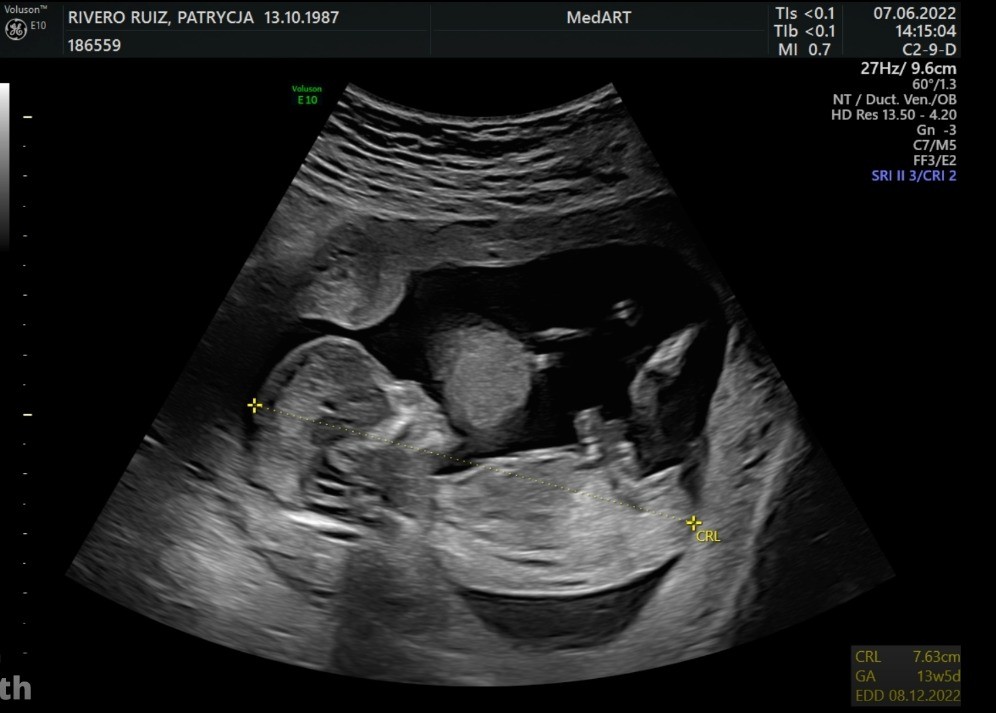

Cześć, u mnie wszystko ok po USG prenatalnym ufff Dziecko rośnie, ma prawie 8 cm, na zdjęciu widać 7,63 ale potem lekarz mierzył z innego ujęcia i już było, że prawie 8 cm. Wszystko na swoim miejscu, zmierzone, proporcjonalne, przepływy krwi wszędzie dobre, serce miarowe tętno 150. Mam filmik na pendrive, w jednym momencie tak słodko wkłada kciuk do ust :) A Wam zostawiam nowe foto mojej dziewczyny :)

• IMG-20220607-WA0001.jpg

IMG-20220607-WA0001.jpg

99,3 KB · Wyświetleń: 151